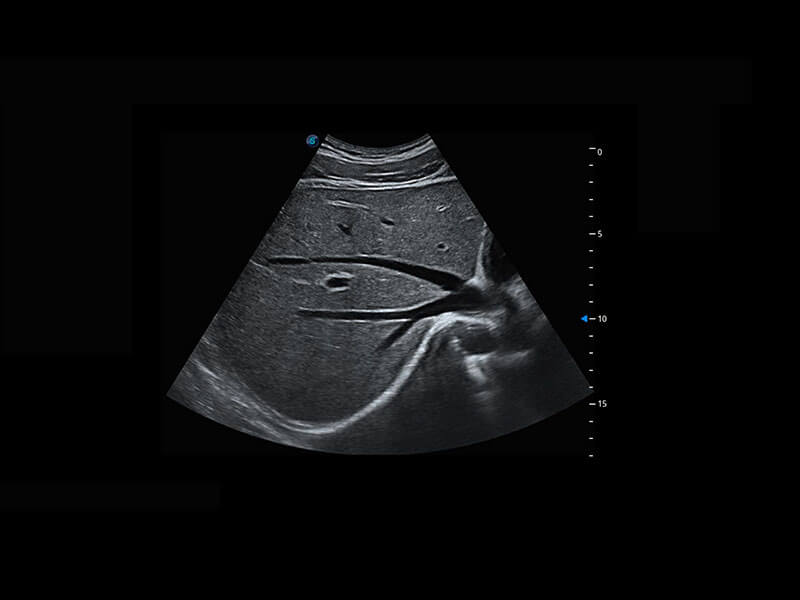

P60为盆底超声检查提供应用方案,多种腔内及腹部容积探头提供从二维、三维到四维的优异图像品质,实时快速三维容积数据获取,专业的测量工具包等人性化设计,为超声医生诊断提供有力保障。

能够简化盆底检查的操作流程,可在二维模式及三维成像模式下实现一键自动提取出标准切面、自动识别当前切面、自动测量,提升盆底检查的高效性,同时也能让青年医生快捷的获得准确的检查结果。